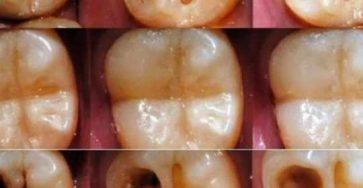

Natural Ways to Maintain Good Dental Health

Are you tired of dealing with the pain and discomfort of cavities? Don’t worry, there are easy and natural ways…